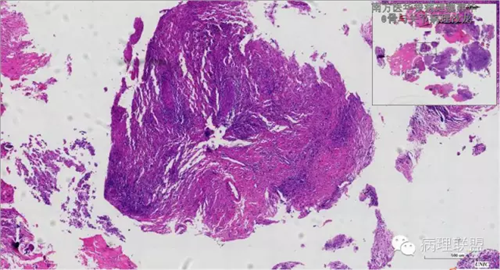

来源于组织细胞的相似性骨病ECD vs RDD 看图说话